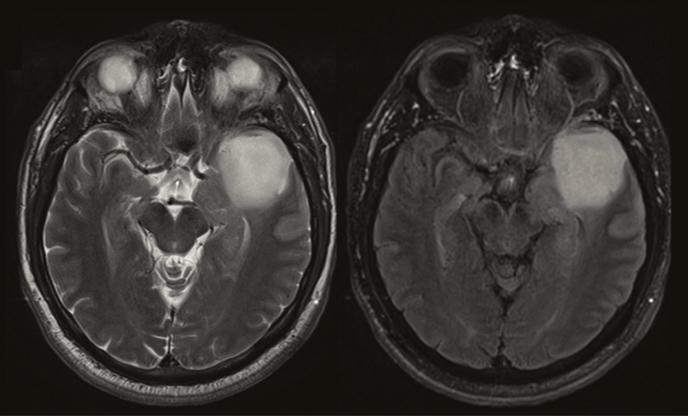

This study aimed to assess the validity and pathophysiology of the T2/FLAIR-mismatch sign for noninvasive identification of isocitrate dehydrogenase (IDH)-mutant 1p/19q non-codeleted glioma.

Magnetic resonance imaging scans from 408 consecutive patients with newly diagnosed glioma (113 lower-grade gliomas and 295 glioblastomas) were evaluated for the presence of T2/FLAIR-mismatch sign by 2 independent reviewers. Sensitivity, specificity, accuracy, positive predictive value (PPV), and negative predictive value (NPV) were calculated to assess the performance of the T2/FLAIR-mismatch sign for identifying IDH-mutant 1p/19q non-codeleted tumors. An exploratory analysis of differences in contrast-enhancing tumor volumes, apparent diffusion coefficient (ADC) values, and relative cerebral blood volume (rCBV) values in IDH-mutant gliomas with versus without the presence of a T2/FLAIR-mismatch sign (as well as analysis of spatial differences within tumors with the presence of a T2/FLAIR-mismatch sign) was performed.

The T2/FLAIR-mismatch sign was present in 12 cases with lower-grade glioma (10.6%), all of them being IDH-mutant 1p/19q non-codeleted tumors (sensitivity = 10.9%, specificity = 100%, PPV = 100%, NPV = 3.0%, accuracy = 13.3%). There was a substantial interrater agreement to identify the T2/FLAIR-mismatch sign (Cohen's kappa = 0.75 [95% CI, 0.57-0.93]). The T2/FLAIR-mismatch sign was not identified in any other molecular subgroup, including IDH-mutant glioblastoma cases ( = 5). IDH-mutant gliomas with a T2/FLAIR-mismatch sign showed significantly higher ADC ( < .0001) and lower rCBV values ( = .0123) as compared to IDH-mutant gliomas without a T2/FLAIR-mismatch sign. Moreover, in IDH-mutant gliomas with T2/FLAIR-mismatch sign the ADC values were significantly lower in the FLAIR-hyperintense rim as compared to the FLAIR-hypointense core of the tumor ( = .0005).

This study confirms the high specificity of the T2/FLAIR-mismatch sign for noninvasive identification of IDH-mutant 1p/19q non-codeleted gliomas; however, sensitivity is low and applicability is limited to lower-grade gliomas. Whether the higher ADC and lower rCBV values in IDH-mutant gliomas with a T2/FLAIR-mismatch sign (as compared to those without) translate into a measurable prognostic effect requires investigation in future studies. Moreover, spatial differences in ADC values between the core and rim of tumors with a T2/FLAIR-mismatch sign potentially reflect specific distinctions in tumor cellularity and microenvironment.

本研究旨在评估T2/液体衰减反转恢复序列(FLAIR)不匹配征对无创识别异柠檬酸脱氢酶(IDH)突变型1p/19q非共缺失型胶质瘤的有效性及病理生理学特征。

由2名独立的评估者对408例新诊断胶质瘤患者(113例低级别胶质瘤和295例胶质母细胞瘤)的磁共振成像扫描进行评估,以确定是否存在T2/FLAIR不匹配征。计算敏感性、特异性、准确性、阳性预测值(PPV)和阴性预测值(NPV),以评估T2/FLAIR不匹配征对识别IDH突变型1p/19q非共缺失型肿瘤的性能。对有和无T2/FLAIR不匹配征的IDH突变型胶质瘤的强化肿瘤体积、表观扩散系数(ADC)值和相对脑血容量(rCBV)值的差异进行探索性分析(以及对存在T2/FLAIR不匹配征的肿瘤内的空间差异进行分析)。

12例低级别胶质瘤(10.6%)存在T2/FLAIR不匹配征,所有这些病例均为IDH突变型1p/19q非共缺失型肿瘤(敏感性=10.9%,特异性=100%,PPV=100%,NPV=3.0%,准确性=13.3%)。在识别T2/FLAIR不匹配征方面,评估者间有高度一致性(Cohen's kappa=0.75[95%CI,0.57-0.93])。在任何其他分子亚组中均未发现T2/FLAIR不匹配征,包括IDH突变型胶质母细胞瘤病例(n=5)。与无T2/FLAIR不匹配征的IDH突变型胶质瘤相比,有T2/FLAIR不匹配征的IDH突变型胶质瘤显示出显著更高的ADC值(P<0.0001)和更低的rCBV值(P=0.0123)。此外,在有T2/FLAIR不匹配征的IDH突变型胶质瘤中,与肿瘤的FLAIR低信号核心相比,FLAIR高信号边缘的ADC值显著更低(P=0.0005)。

本研究证实了T2/FLAIR不匹配征对无创识别IDH突变型1p/19q非共缺失型胶质瘤具有高特异性;然而,敏感性较低且适用性仅限于低级别胶质瘤。与无T2/FLAIR不匹配征的IDH突变型胶质瘤相比,有T2/FLAIR不匹配征的IDH突变型胶质瘤中更高的ADC值和更低的rCBV值是否转化为可测量的预后效应,需要在未来的研究中进行探究。此外,有T2/FLAIR不匹配征的肿瘤核心与边缘之间ADC值的空间差异可能反映了肿瘤细胞密度和微环境的特定差异。